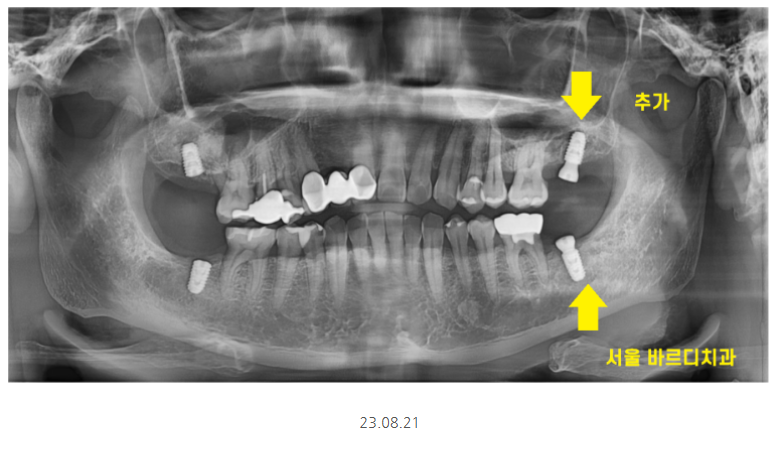

나란히 임플란트 위아래 한 번에 완성되었습니다.

어금니 4개가 새로 생기셨으니

맛있는 거 더 많이 드실 수 있겠습니다.